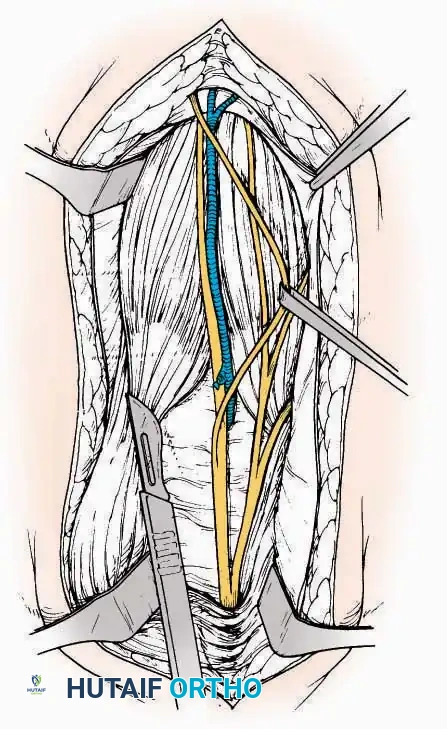

Anterolateral Approach

The anterolateral approach is widely considered the "universal incision" for the foot and ankle. It provides unparalleled access to the ankle joint, the talus, and the majority of the tarsal articulations, while safely avoiding the major anterior neurovascular bundle. The only tarsal joints inaccessible via this route are the naviculocuneiform joints (specifically the medial and intermediate).

Indications: Total talectomy, triple arthrodesis, ankle arthrodesis, and open reduction of complex talar neck fractures.

Surgical Technique:

* Incision: Begin over the anterolateral aspect of the leg, medial to the fibula and 5 cm proximal to the ankle joint line. Carry it distally over the joint, crossing the anterolateral aspect of the talar body and the calcaneocuboid joint, terminating at the base of the fourth metatarsal.

* Superficial Dissection: Incise the superficial fascia and the superior and inferior extensor retinacula down to the periosteum of the tibia and the ankle joint capsule.

* Vascular Ligation: This trajectory usually requires the identification and ligation of the anterolateral malleolar and lateral tarsal arteries.

* Nerve Protection: Retract the skin edges carefully. Identify and protect the intermediate dorsal cutaneous branches of the superficial peroneal nerve (SPN), which frequently cross the distal aspect of this incision.

* Muscle Management: Identify the origin of the extensor digitorum brevis (EDB) muscle on the lateral calcaneus. Divide it in the direction of its fibers, or detach its origin entirely and reflect it distally to expose the subtalar and calcaneocuboid joints.

* Deep Exposure: Retract the extensor digitorum longus (EDL) tendons, the dorsalis pedis artery, and the deep peroneal nerve (DPN) medially. Incise the anterior ankle capsule to expose the tibiotalar joint.

* Tarsal Exposure: Expose the talonavicular joint by dissecting deep to the extensor tendons and incising its capsule transversely. Continue laterally through the capsule of the calcaneocuboid joint. By excising the fat pad within the sinus tarsi (lateral and inferior to the talar neck), the posterior facet of the subtalar joint is brought into direct view.